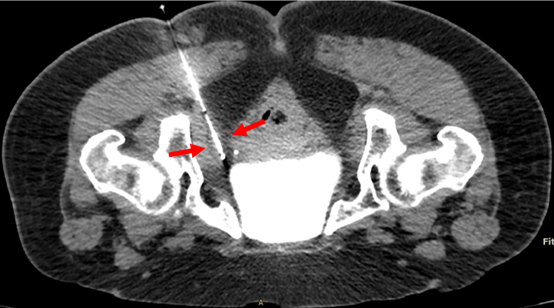

![]() 圖三:進行冷凍當中,術中評估冰球形成,確認冰球包覆神經所在位置(箭頭)